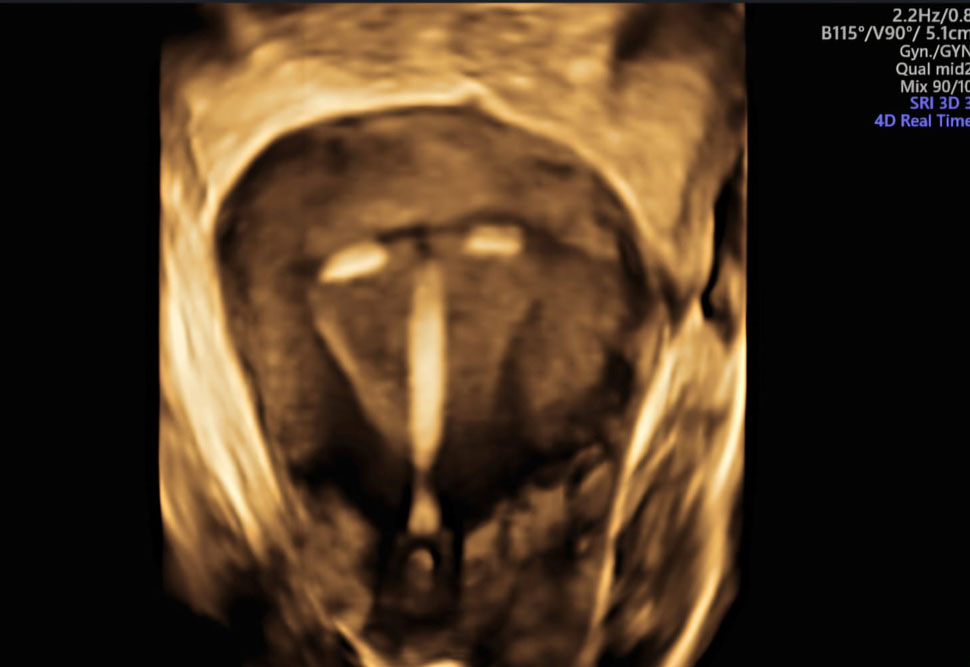

✔️ Ensures the baby is receiving enough oxygen and nutrients

✔️ Evaluates blood flow in the placenta

✔️ Checks blood supply to the baby’s brain and heart

✔️ Helps with early detection of:

Fetal growth restriction – Low oxygen levels – Fetal anemia – Effects of high blood pressure or diabetes during pregnancy